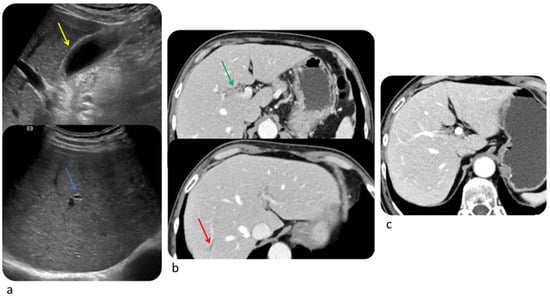

6.2. Liver